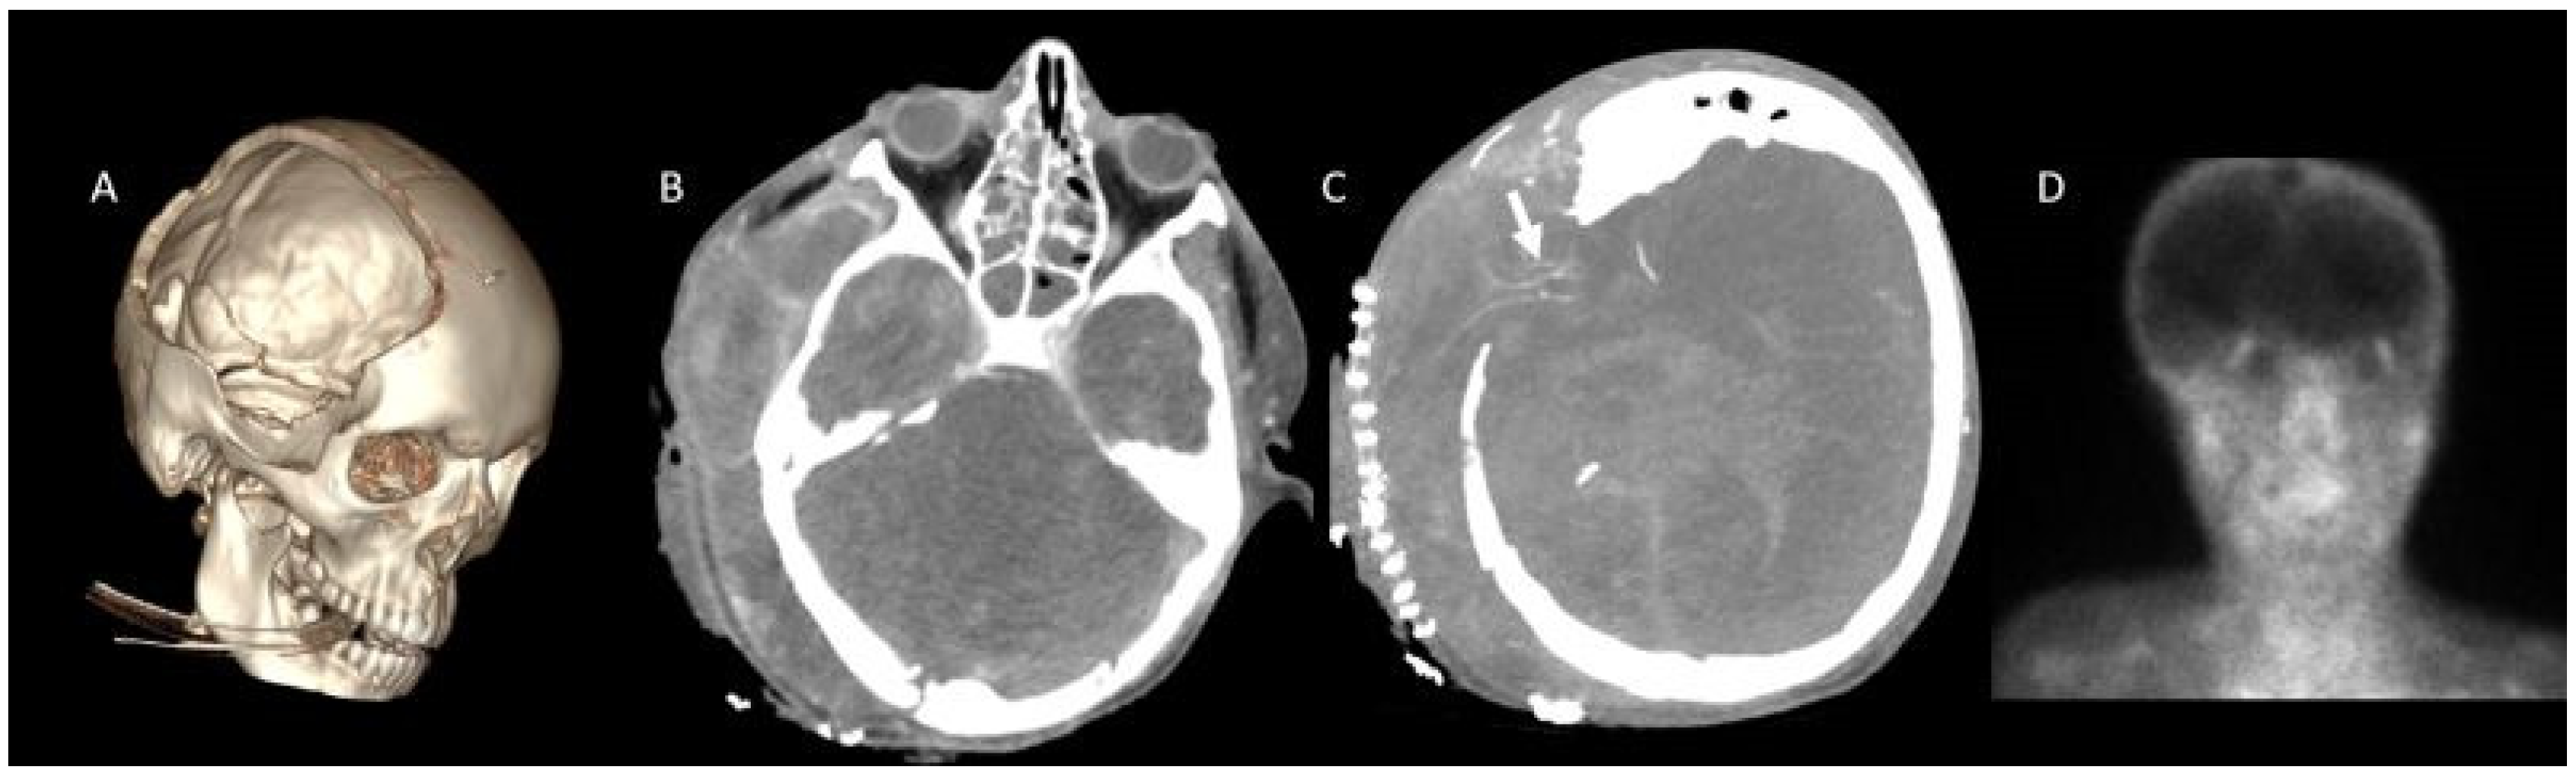

- A60-V60: Absence of opacification in M4 branches of the middle cerebral arteries (MCAs) and ICVs in the venous phase, based on the reference 4-point system by Frampas et al. [11].

- A20-V60: Absence of opacification in M4 branches of the MCAs in the arterial phase and ICVs in the venous phase, based on the revised arteriovenous scoring system by Nunes et al. [12].

- ICV-SPV: Absence of opacification in the ICVs and SPVs in the venous phase, based on the revised venous scoring system by Marchand et al. [10].

- Nunes, D.M.; Maia, A.C.M., Jr.; Boni, R.C.; da Rocha, A.J. Impact of skull defects on the role of CTA for brain death confirmation. AJNR Am. J. Neuroradiol. 2019, 40, 1177–1183. [Google Scholar] [CrossRef] [PubMed]